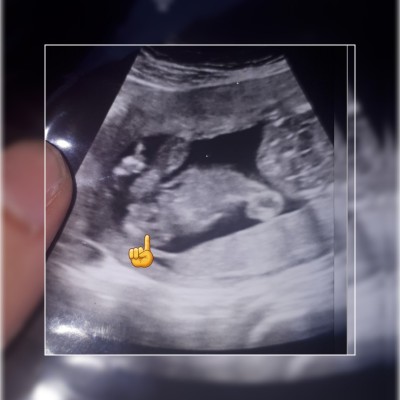

Merhaba cnım anneler 16 haftada yüzde 99 erkek deyip cıkıntısının bu oldugnu söyledi doktr sizce değisr mi artık cinsiyet biseyler almak istyorum

image

Cinsiyet değişmez önce Bi şunda anlaşalım :)  doktorun tahmini değişebilir belki ama var olan da değişmez yani :) kimisi doğunca yanlış tahmin olduğunu görüyor :) Allah sağlıkla kavuşmayı nasip etsin